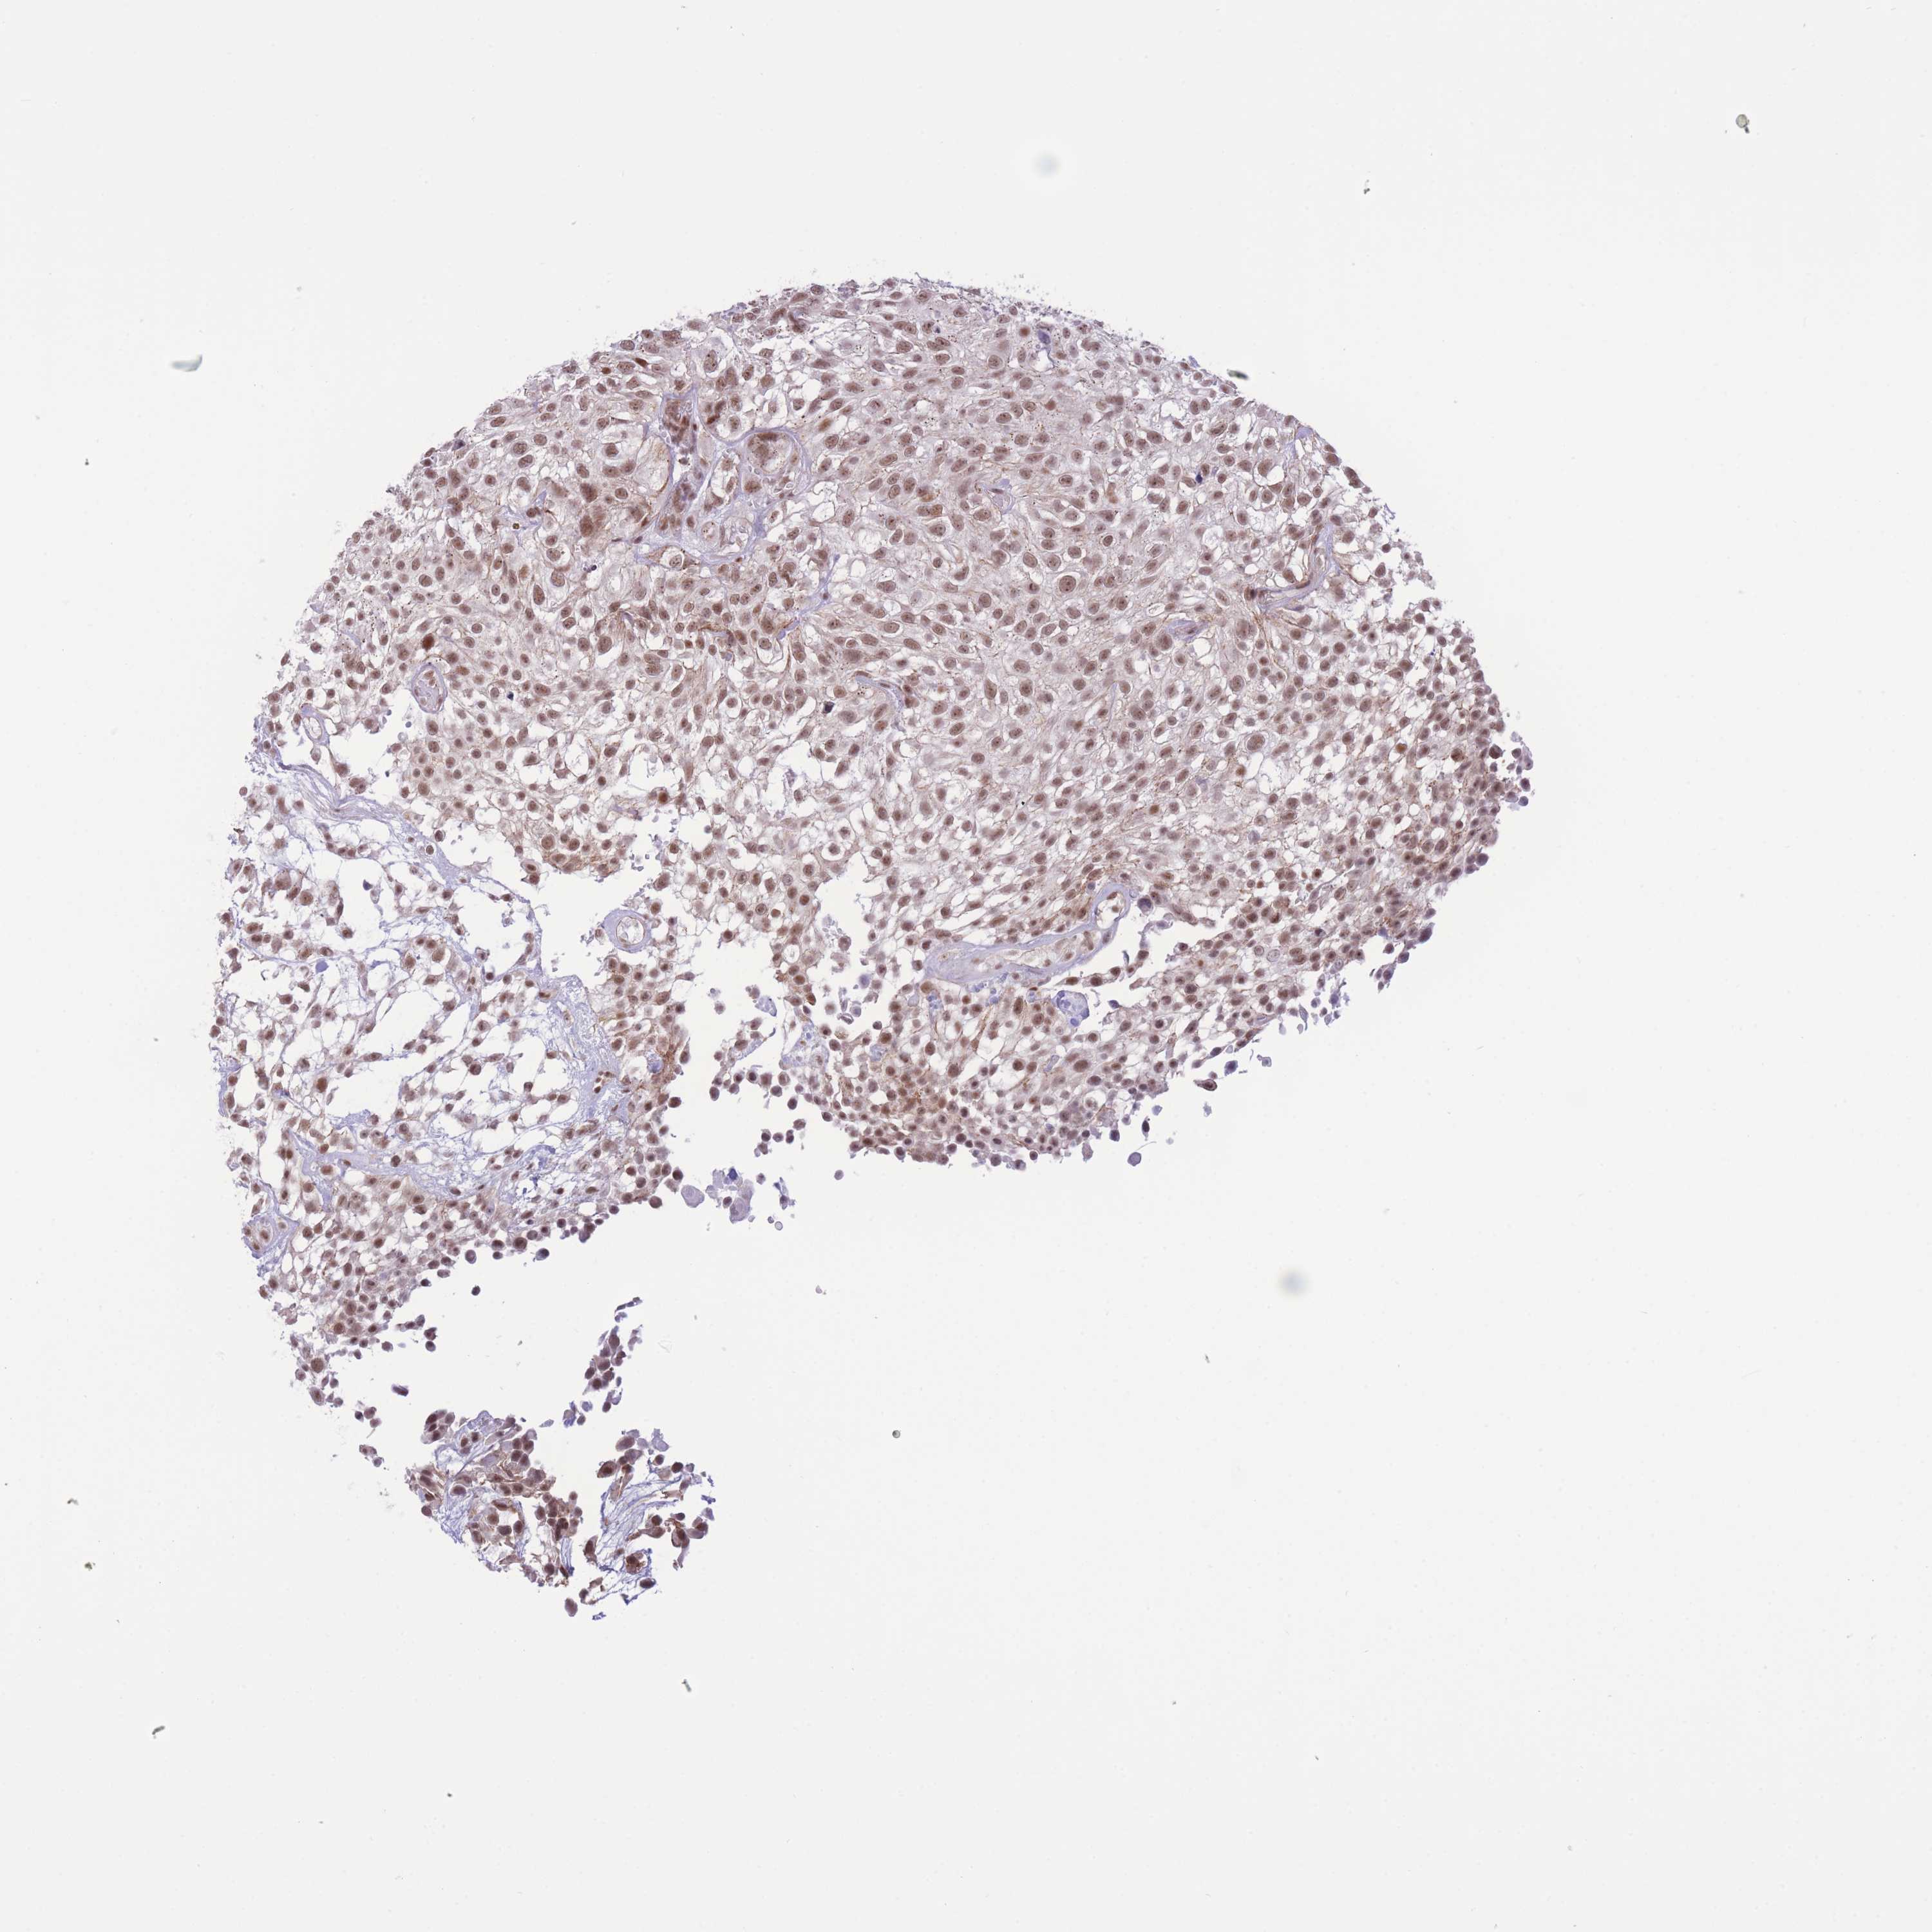

UROTHELIAL CANCER - Protein expressioni

A mouse-over function shows sample information and annotation data. Click on an image to view it in a full screen mode. Samples can be filtered based on level of antibody staining by selecting one or several of the following categories: high, medium, low and not detected. The assay and annotation is described here.

Note that samples used for immunohistochemistry by the Human Protein Atlas do not correspond to samples in the TCGA dataset.

Antibody stainingi

Antibody staining in the annotated cell types in the current human tissue is reported as not detected, low, medium, or high, based on conventional immunohistochemistry profiling in selected tissues. This score is based on the combination of the staining intensity and fraction of stained cells.

Each image is clickable and will lead to virtual microscopy that enables deeper exploration of all samples and also displays staining intensity scores, fraction scores and subcellular localization as well as patient and tissue information for each sample.

Antibody HPA049517

Staining

High

Medium

Low

Not detected

Intensity

Strong

Moderate

Weak

Negative

Quantity

>75%

75%-25%

<25%

None

Location

Nuclear

Cytoplasmic/membranous

Cytoplasmic/membranous,nuclear

Urothelial carcinoma, High grade

Urothelial carcinoma, Low grade